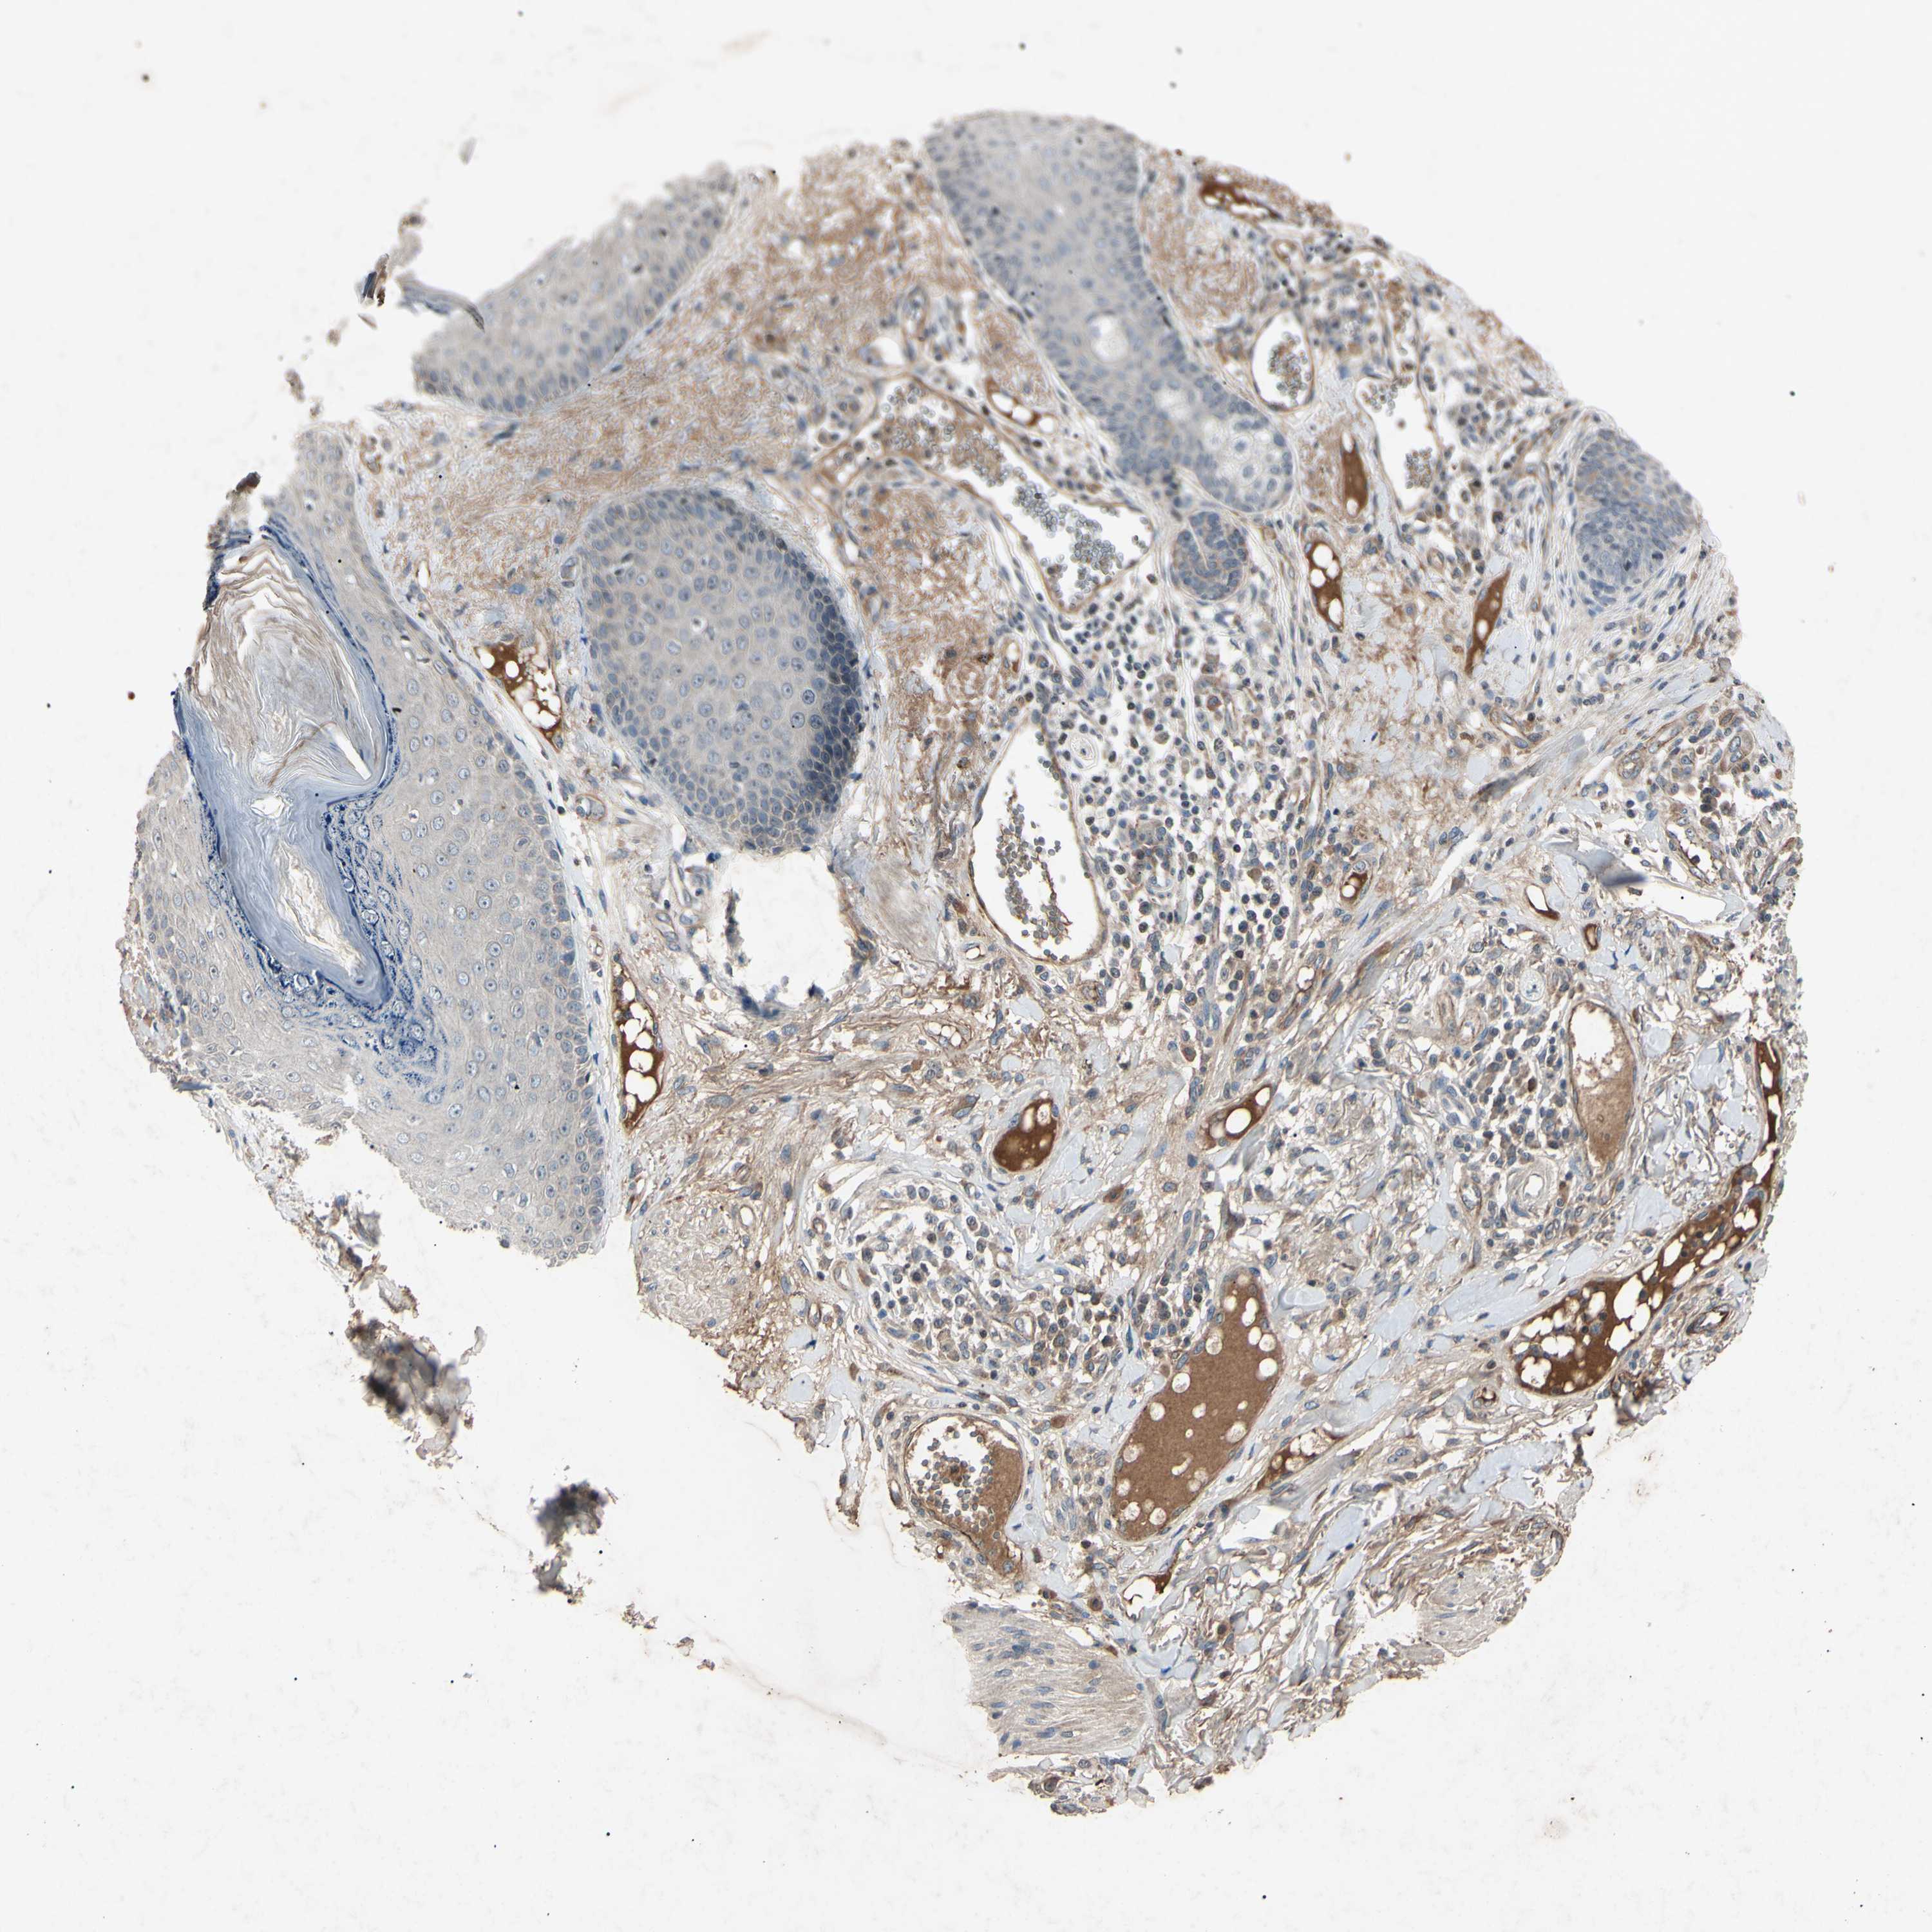

CANCER SKIN CANCER Show tissue menu

SKIN CANCER - Protein expressioni

A mouse-over function shows sample information and annotation data. Click on an image to view it in a full screen mode. Samples can be filtered based on level of antibody staining by selecting one or several of the following categories: high, medium, low and not detected. The assay and annotation is described here.

Antibody stainingi

Antibody staining in the annotated cell types in the current human tissue is reported as not detected, low, medium, or high, based on conventional immunohistochemistry profiling in selected tissues. This score is based on the combination of the staining intensity and fraction of stained cells.

Each image is clickable and will lead to virtual microscopy that enables deeper exploration of all samples and also displays staining intensity scores, fraction scores and subcellular localization as well as patient and tissue information for each sample.

Antibody HPA063595

Antibody HPA064970

Antibody CAB009966

Staining

High

Medium

Low

Not detected

Basal cell carcinoma

Squamous cell carcinoma, NOS